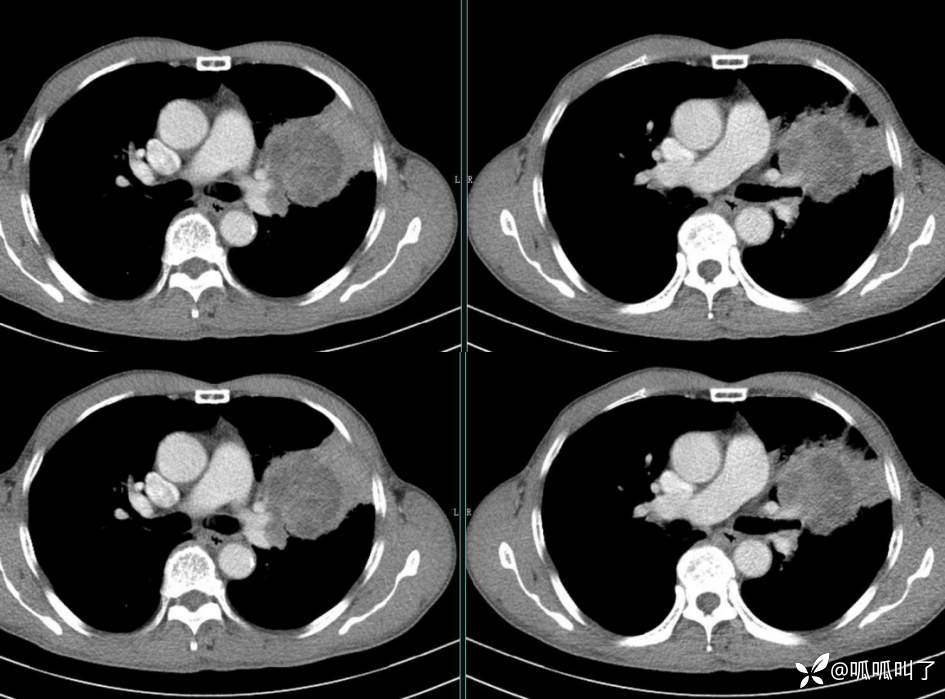

胸部CT平扫和增强: